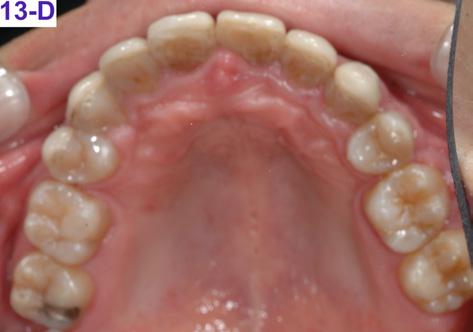

FIG. 13D: Post-treatment, maxilla, occlusal view

Please view the post-treatment images at the time of insertion of the retainers (Figure 13 – A, B, C. D, E, F, G, H, I, J, K, L).